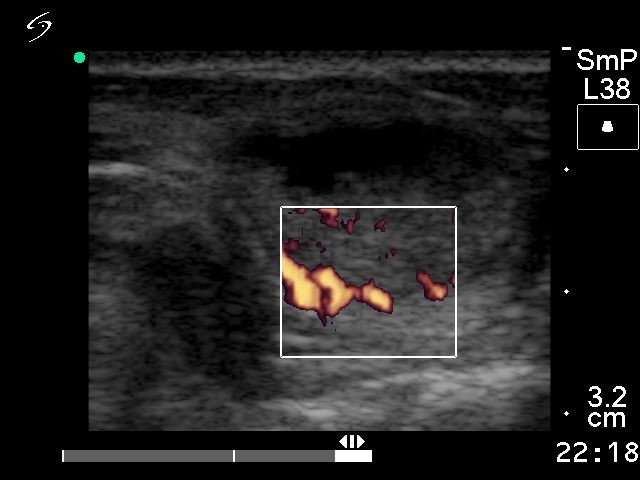

Ultrasonography revealed a mixed solid-cystic nodule in the enlarged left lobe.